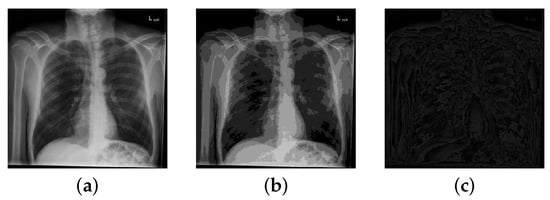

4.1. Visual Evaluation